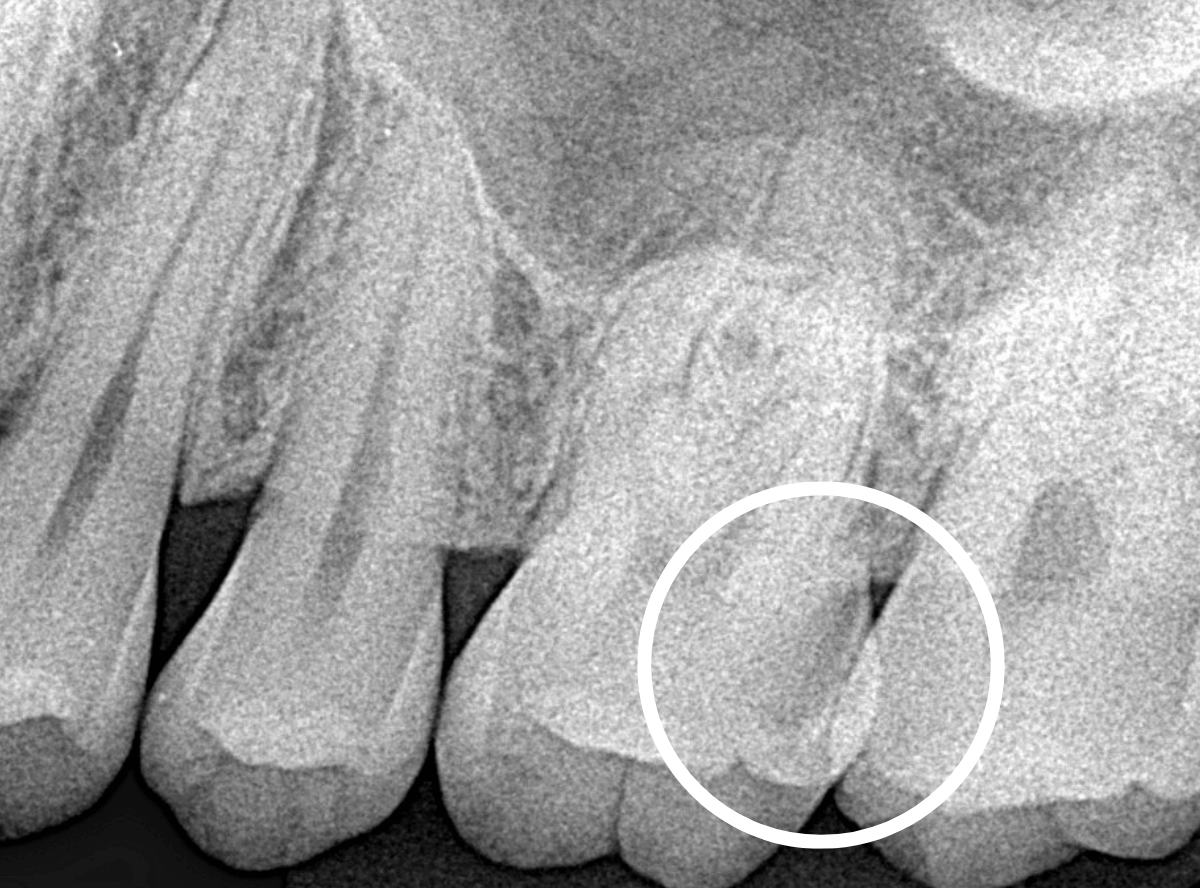

Case.25 レントゲン所見と目視を頼りに、虫歯治療

検査時に〇部、歯と歯の間の小臼歯部に虫歯らしき黒い影があるのが見つかりました。

かなり怪しいですが、メタル・インレーが入ってるので、それが透けている可能性もあります。

レントゲン写真で確認します。

レントゲンでは後ろの大臼歯部の方が虫歯になっているように見え、小臼歯部は問題ないように見えます。